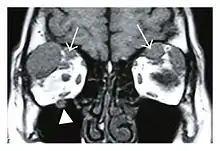

![]() Bilateral supraorbital nerve enlargements (arrows) and right infraorbital nerve (arrow head) enlargement in a 47-year-old woman with a serum IgG4 of 1000 mg/dL.[1] (T1-weighted MRI) |